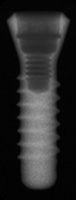

Straumann ITI

Standard Plus RN

Connection Interface

Internal interface

Body Shape

Non-tapered body

Thread Design

ThreadedV-shaped threads

Additional Features

Curved apexFlared flangeimplantWider flange